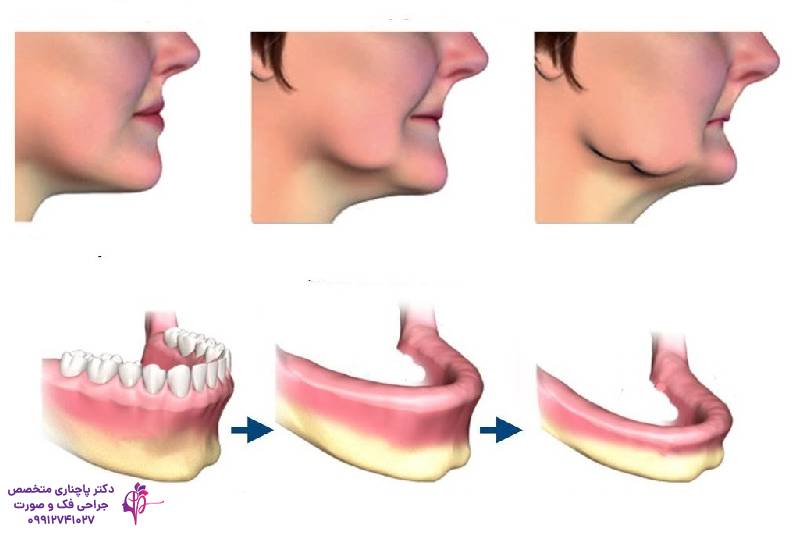

- احساس جمع شدن دهان به سمت داخل صورت یکی از اولین نشانههای مشکلات دندانی و کاهش حجم استخوان فک است. در این شرایط چانه برجستهتر به نظر میرسد و گونهها دچار فرورفتگی میشوند. دلیلش این است که دیگر استخوان فک نمیتواند بافتهار نرم صورت را حمایت کند و در نتیجه ظاهر پیرتر به نظر میرسد.

- چین و چروکهای عمیق اطراف دهان و لبها نیز یکی از علائم تحلیل استخوان فک است. همانطور که گفتیم با کم شدن حجم استخوانها دیگر بستر مناسبی برای بافتها و عضلات صورت وجود ندارد و در نتیجه بافتها دچار چین و چروکهای عمیق میشوند.

- نازکتر به نظر آمدن لبها و پیری زودرس صورت را احتمالا در خیلی از افراد سن بالایی که دندانهای سالمی هم ندارند دیدهاید. وقتی زیر عضلات و پوست صورت استخوان کافی وجود ندارد لبها کمکم نازک میشوند و صورت خیلی پیرتر از سن واقعی خودش به نظر میرسد.

کم شدن تراکم بافت استخوانی را میتوان بر اساس مکان و شدت آن به چند نوع تقسیم کرد: تحلیل افقی، تحلیل عمودی، تحلیل موضعی و تحلیل کلی. در تحلیل افقی اول عرض استخوان کم میشود که معمولا با از دست رفتن دندانها اتفاق میافتد و در ادامه فک باریک میشود. وقتی تحلیل افقی اتفاق میافتد استخوان فک دیگر توان نگه داشتن پروتزها را ندارد. در تحلیل عمودی ولی اول ارتفاع استخوان فک کم میشود و باعث فرو رفتن صورت و کوتاه شدن فاصله بین بینی و چانه میشود. در تحلیل ترکیبی نیز هر دو مدل افقی و عمودی با هم اتفاق میافتد که نیاز به درمانهای پیچیدهتری هم دارد. تحلیل موضعی عموما در یک ناحیه اتفاق میافتد و دلیلش عمدتا عفونت یا ضربه است اما میتواند خیلی سریع رشد کند. تحلیل کلی، که کل فک را درگیر میکند و اغلب با بیماریهای جسمی مثل پوکی استخوان مرتبط است.

تحلیل استخوان فک بالا معمولا به مشکلات سینوسی ارتباط دارد. سینوسهای فکی میتوانند بعد از کشیدن دندانهای مولر فشار بیشتری به فک وارد کنند و باعث سریعتر شدن تحلیل رفتن فک شوند. در این نوع تحلیل دندانهای بالایی لق میشوند و جویدن برای بیمار سخت میشود. تغییرات ظاهری مثل فرو رفتن گونهها و جمع شدن لبها از علائم تحلیل استخوان فک بالا هستند. برای درمان تحلیل استخوان فک بالا معمولا پیوند استخوان فک انجام میشود. پس از پیوند استخوان فک بیمار میتواند ایمپلنت یا پروتز انجام دهد.

علائم و درمان تحلیل استخوان فک پایین

تحلیل فک پایین بیشتر روی حرف زدن و جویدن فرد تاثیر دارد. فک پایین مهمترین نقش را در حرکت فک دارد و ضعیف شدن آن طبیعتا تاثیر منفی روی این عملکردها دارد. برجسته شدن چانه و ناهماهنگی در ظاهر از علائم تحلیل استخوان فک پایین است. علاوه بر اینکه به دلیل نبود استخوان کافی دندانها لق میشوند و استفاده از پروتز هم سختتر میشود. برای درمان تحلیل استخوان فک پایین معمولا ایمپلنت را پیشنهاد میکنند. ایمپلنتها استخوان فک را تحریک کرده و با حفظ ساختار آن جلوی پیشرفت تحلیل را میگیرند.